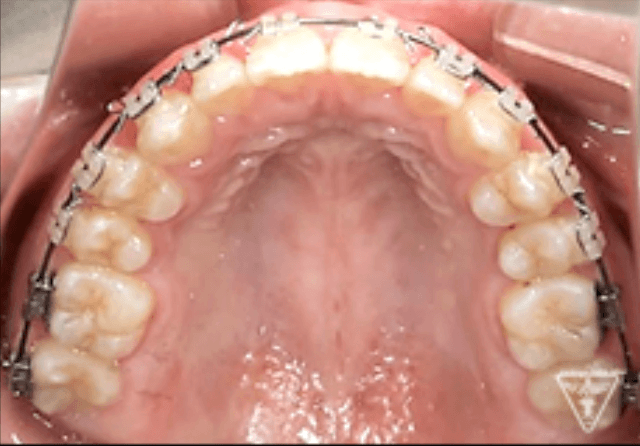

矯正器具 装着時の治療過程

初期